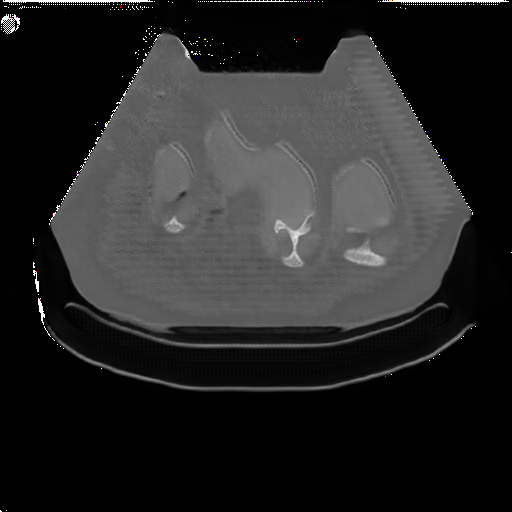

The Abdomen-1K dataset provides more than 1000 CT scans, and the data is provided in 3D format. Firstly, we randomly select 200 CT scans, and for each CT scan, we randomly sampled 10 transverse plane slices. For a more uniform image shape, we applied a fan shape mask to the CT images to mimic the outline of convex ultrasound images.

Fig. 5 and 6 present examples of the translation results from CT to ultrasound. These visual comparisons demonstrate that the S-CycleGAN can not only mimic the ultrasound style but also preserve critical anatomical features compared with Fig. 3. The synthetic images closely resemble real ultrasound scans in terms of texture and shape, suggesting a high level of detail preservation.

Refer to caption

(a) Real CT

(b) Fake US

(c) CT Label

(d) Predicted US Mask

Figure 5: CT-to-ultrasound translation example.1